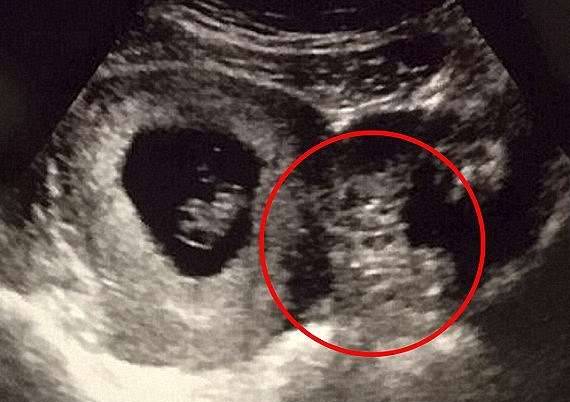

▼还有人在超声波照片中发现了亚瑟王的脸,这个宝宝也被取名为亚瑟。